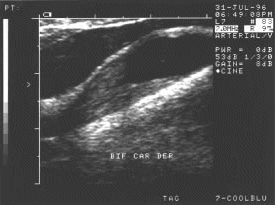

Figura 24.- Oclusión de la arteria carótida interna en el bulbo. La luz del vaso se encuentra ocupada por material homogéneo isoecogénico.